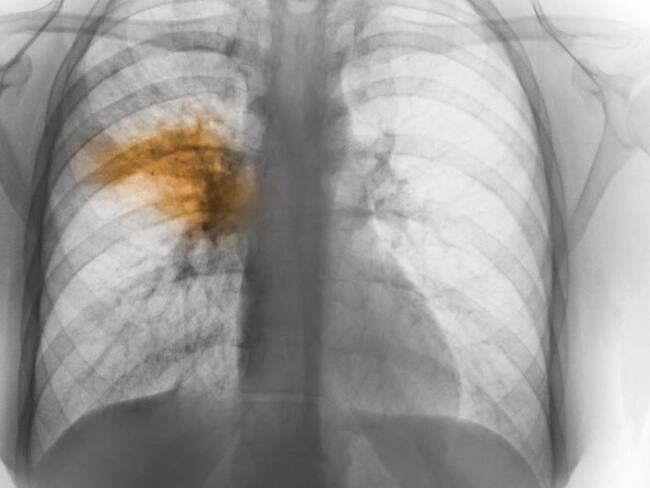

Sanatorio en Argentina fue aislado por casos de neumonía de origen desconocido

Dos personas fallecieron por la neumonía bilateral

Las autoridades sanitarias de Tucumán, en el norte de Argentina, ordenaron el aislamiento preventivo por siete días del Sanatorio Luz Médica, ubicado en donde se detectaron seis casos de neumonía bilateral cuyo origen es desconocido.

Según informó el Ministerio de Salud de Argentina, los seis casos registrados corresponden a cinco trabajadores de la salud y a una paciente que iniciaron síntomas entre el 18 y el 22 de agosto.

Hasta el momento, los casos mortales son dos, sin embargo el ministro de salud pública, Luis Medina Ruiz, aseguró que desde el 22 de agosto no se registran nuevos casos.